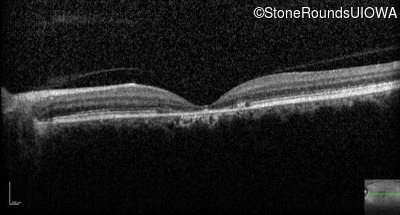

Optical Coherence Tomography - Right - 20/125 -1

Exemplar / OCT Stack

OCT Stack